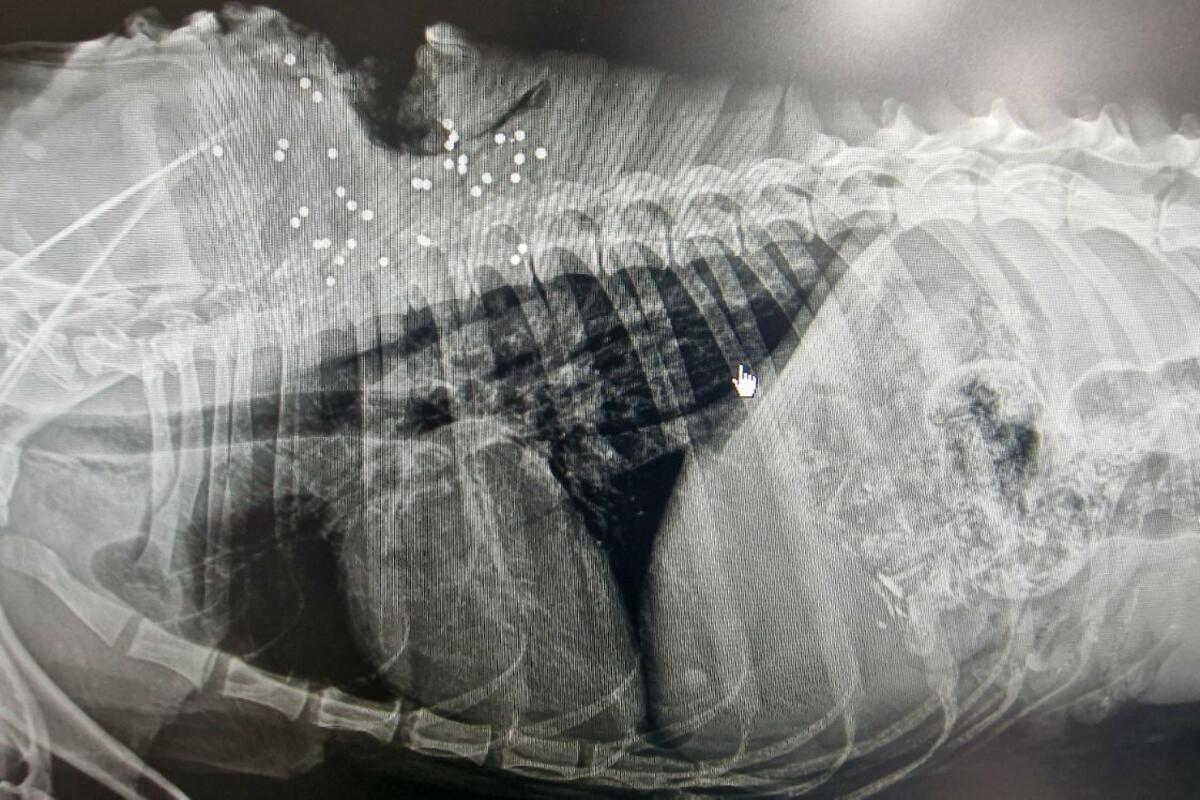

Rentgen potvrdio da je pas ranjen vatrenim oružjem, Foto: Privatna arhiva

Da je ženka o kojoj vodi računa ranjena vatrenim oružjem, navedeno je i u izvještaju veterinara, u kojem se, nakon snimanja rentgenom, pored ostalog, potvrđuje prisustvo zrna od metka.

“Nije je bilo šest, sedam dana. Voljela je da skita sa vlasničkim psom iz komšiluka. Kad sam došla, bila je nagrđena, rana užasna, mislila sam da je od sjekire. Povela sam je kod veterinara, snimili su joj leđa, sanirali ranu. Čudili su se od čega je rana, a nakon što su je snimili, snimak je pokazao da je u psa izbliza pucano iz sačmarice... Čudili su se i kako joj nisu pluća probijena, jer je pucano iz blizine. Zamislite samo tu bol i kroz šta pas prolazi, kroz šta je prošao... Druga joj nema, sigurno je negdje mrtav, jer se nisu razdvajali”, navela je ona.